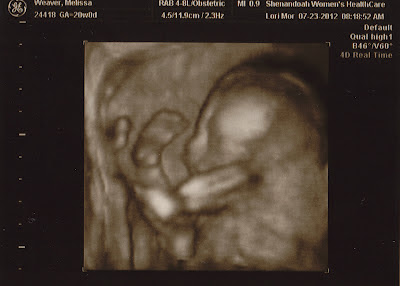

Monday, July 23, 2012

It's a....

... GIRL!!!

More pictures to come later, but this is a sneak peek :) Thanks to Melody Mersiovsky for her AMAZING photography (and for passing on the idea)! We are so blessed. Thank you, Jesus.